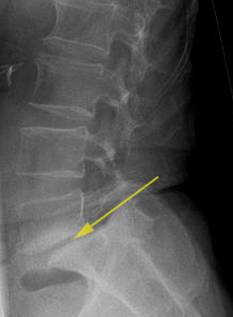

Zusätzlich zur klinischen und neurologischen Untersuchung zieht der Rückenspezialist bildgebende Verfahren heran. Unerlässlich zum Nachweis einer Wirbelkanalstenose ist – neben der obligatorischen Röntgenuntersuchung – eine Magnetresonanztomografie (MRT).

Die MRT zeigt z. B. die einengenden Spondylophyten oder die Vorwölbung einer höhenverminderten, dehydrierten Bandscheibe in den Spinalkanal hinein. Manchmal sind auch mehrere Stenosen sichtbar. Nur durch genaue Abstimmung der radiologischen Befunde mit den Ergebnissen der neurologischen Untersuchung und der Beschwerden des Patienten lässt sich die klinische Relevanz der sichtbaren Engstellen deuten.

- Überbeweglichkeit (Spondylolisthesis) der Wirbelkörper (bei Aufnahmen in Beuge- und Streckstellung der Wirbelsäule)